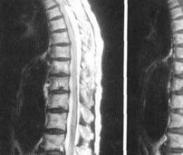

脊髓前綜合征癥狀

• 脊髓前綜合征

628健康網(wǎng)為您分享有關(guān)脊髓前綜合征的癥狀,脊髓前綜合征的治療方法,脊髓前綜合征的預(yù)防知識,脊髓前綜合征的癥狀圖片,脊...